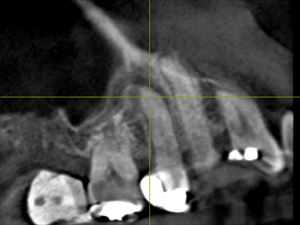

歯科ドックのCTにこれも病巣が!

左上の5番の根尖に病巣。根管充填が中途半端。根管は狭窄していないようなのになぜ?